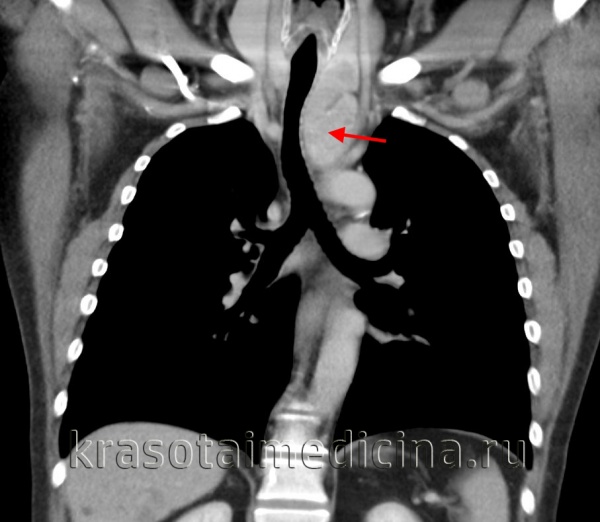

а) Первичные саркомы сердца. Первичные саркомы сердца - наиболее часто встречающиеся (95%) первичные злокачественные опухоли сердца. Они происходят из мезенхимных клеток. Обследуя больных в связи с подозрением на первичную саркому сердца, всегда необходимо также исключить метастазы экстракардиальной опухоли, исходящей из костей скелета или ретроперитонеума. Метастазы саркомы в сердце наблюдаются в 60 раз чаще, чем первичные саркомы сердца. Из клинических проявлений следует отметить затруднение дыхания, боль в груди, симптомы тампонады сердца, реже наблюдаются эмболии, обмороки или внезапная сердечная смерть. Саркому сердца в 75% случаев удается диагностировать с помощью двумерной ЭхоКГ.

Диагностике помогает наличие одновременно выпота в полости перикарда. Для установления диагноза можно выполнить также КТ или МРТ. Роль чреспищеводной ЭхоКГ особенно значительна при локализации опухоли в предсердии. Дифференциальная диагностика с миксомой предсердия упрощается в случае, когда опухоль инфильтрирует стенку желудочка. Присутствие очагов обызвествления наблюдается как в саркомах, так и в миксомах, поэтому данный признак не используется для проведения дифференциальной диагностики.

1. Ангиосаркомы. Ангиосаркомы - наиболее часто встречающиеся саркомы сердца у взрослых. Они локализуются преимущественно в правом предсердии. Часто в опухолевый процесс вовлекается перикард, но нередки также случаи, когда опухолевая инфильтрация распространяется на полые вены и на трехстворчатый клапан. Средний возраст больных с саркомой сердца составляет 40 лет. У мужчин ангиосаркомы встречаются чаще, чем у женщин. Прогноз жизни при ангиосаркоме весьма неблагоприятный. После установления диагноза продолжительность жизни больных составляет лишь 3-4 мес., и изменить прогноз удается лишь путем ранней диагностики ангиосаркомы и радикального ее иссечения.